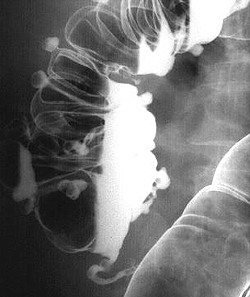

Рентгенографическое исследование толстого кишечника с барием (ирригоскопия) позволяет диагностировать дивертикулит, если невозможно проведение колоноскопии, или она дает неоднозначные результаты. Дивертикулы на рентгенографии определяются в виде образований округлой формы, которые имеют диаметр от 0,5 до 5 см. При дивертикулите на рентгенограмме визуализируются одиночные и множественные выпячивания, а края дивертикулов имеют неровные зазубренные контуры. Если на фоне данного патологического состояния происходит перфорация дивертикула с формированием свища, то при проведении рентгенографии свищ будет визуализироваться в виде контрастирующегося тяжа, который распространяется в направлении других органов.

- Рентгенодиагностика. Пациенты с данным заболеванием требуют проведения ирригографии, желательно с двойным контрастированием. На рентгеновском снимке будут видны выпячивания кишечной стенки, сообщающиеся с полостью кишечника. Следует помнить, что при наличии осложнений дивертикулов кишечника сначала необходимо сделать обзорную рентгенографию органов брюшной полости, убедиться в отсутствии признаков перфорации, и лишь затем назначать ирригографию.

Ирригоскопия:

Одним из наиболее доступных методов диагностики является ирригоскопия, позволяющая достоверно выявить локализация, размеры и количество дивертикулов.